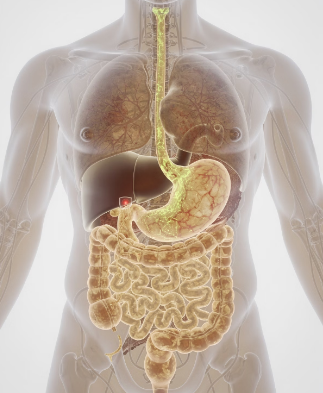

4단계: 위산 역류·알레르기·기타 원인

역류성 식도염으로 위산이 식도와 기도 주변 신경을 자극하면 식후에 가래가 심해지는 독특한 가래가 생기는 원인이 된다. 비염, 알레르기, 천식이 있는 사람은 상기도와 기관지에 염증이 반복되며 아침·밤에 특히 심한 가래와 기침이 나타나는 가래가 생기는 원인을 경험하기 쉽다.

이처럼 가래가 생기는 원인은 호흡기 외에도 소화기, 알레르기 질환과 연결될 수 있어 증상 패턴을 잘 관찰하는 것이 중요하다.